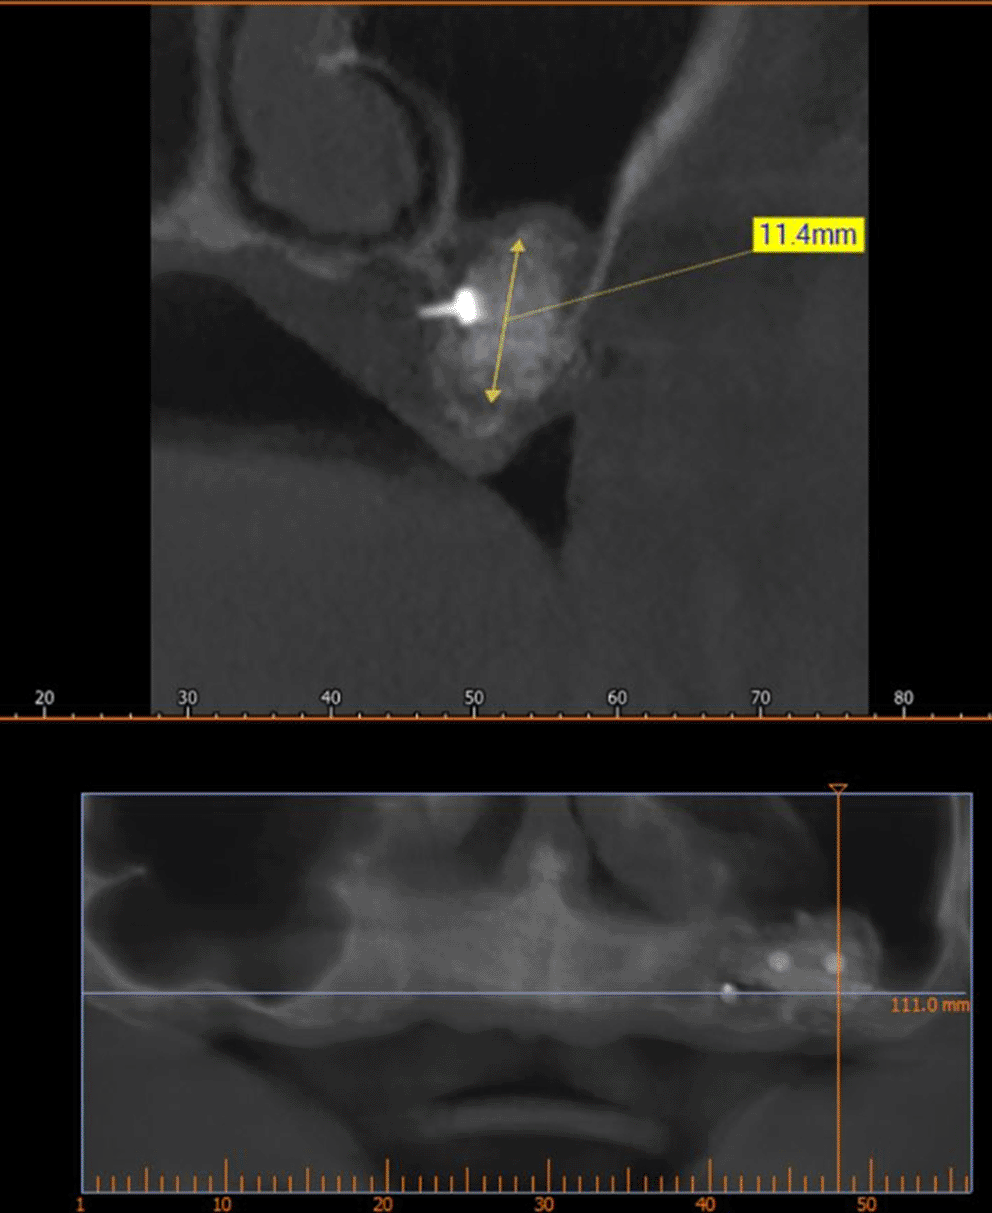

A CBCT scan was performed immediately after grafting and showed a direct bone gain of (11.4 mm) ( Figure 10) and 9 months after bone grafting where subsequent bone gain (11.4 mm) was found ( Figure 11).

72a8e8c6-ed30-422d-8d84-4a8b8f46f6f2_figure10.gif

Figure 10. CBCT after grafting immediately.